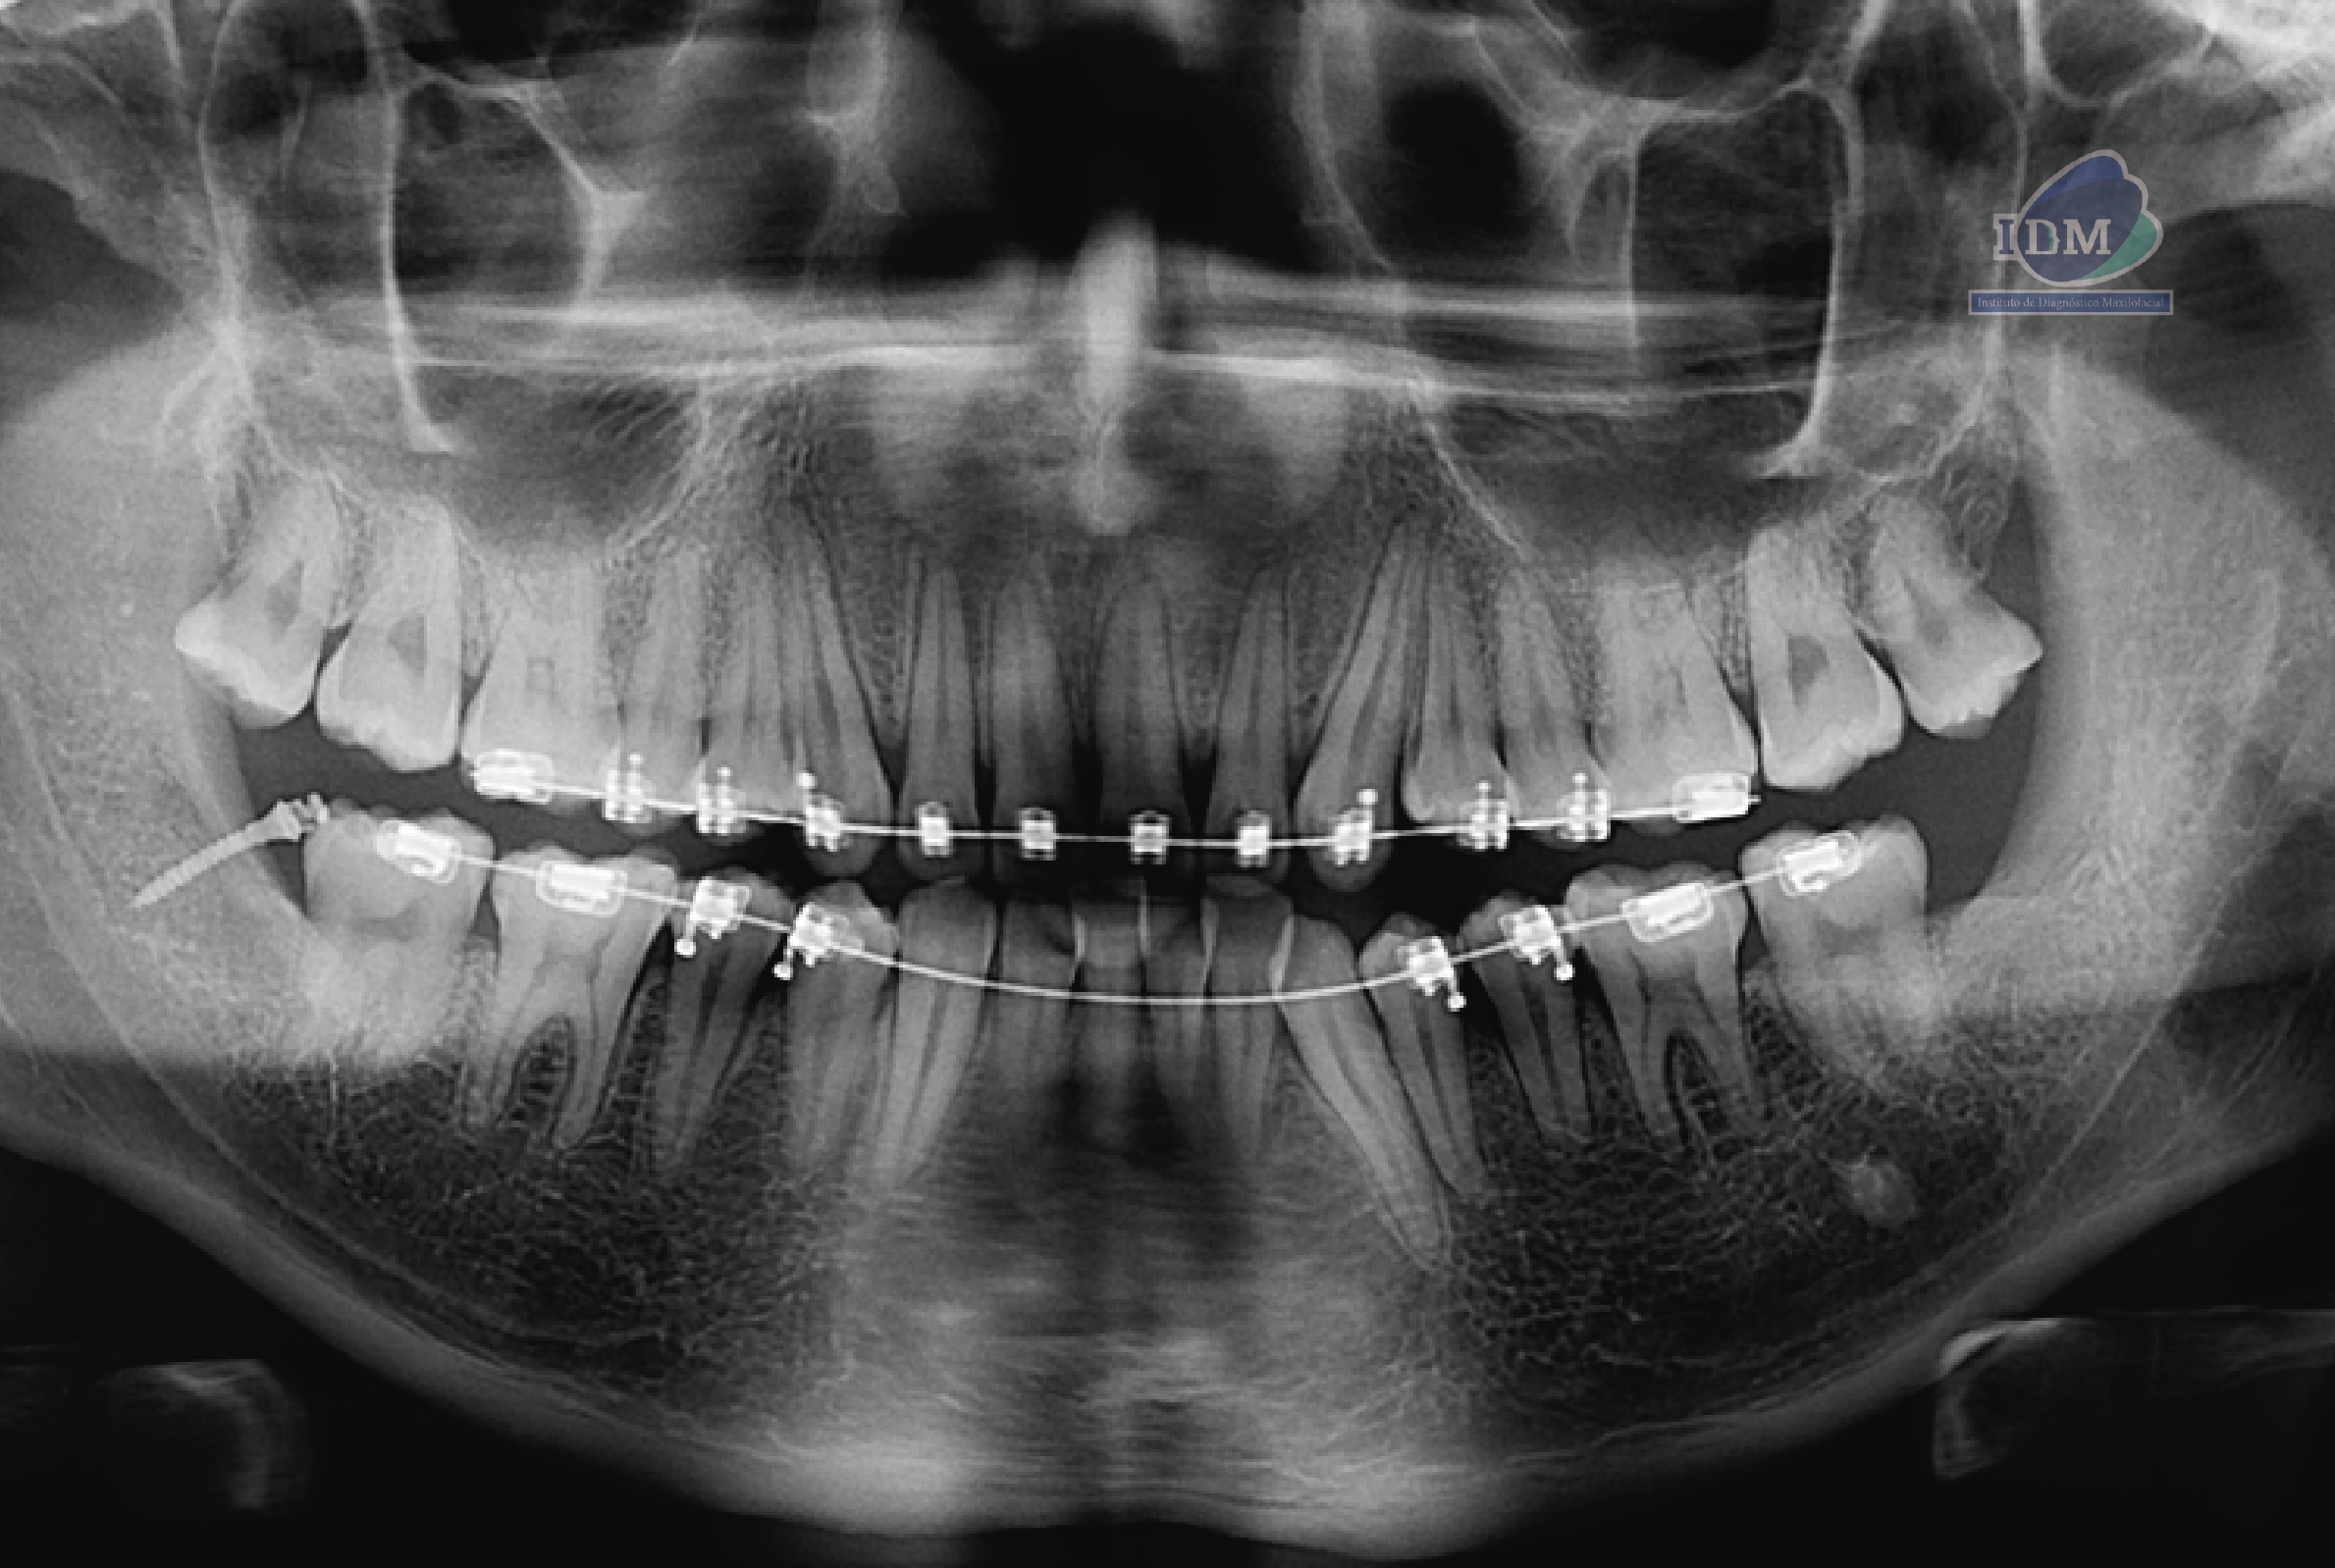

En la radiografía panorámica (Figura 1), se aprecia imagen radiopaca proyectada sobre línea media.

Radiografia Panorámica

caso 328 idm raciografia panoramica